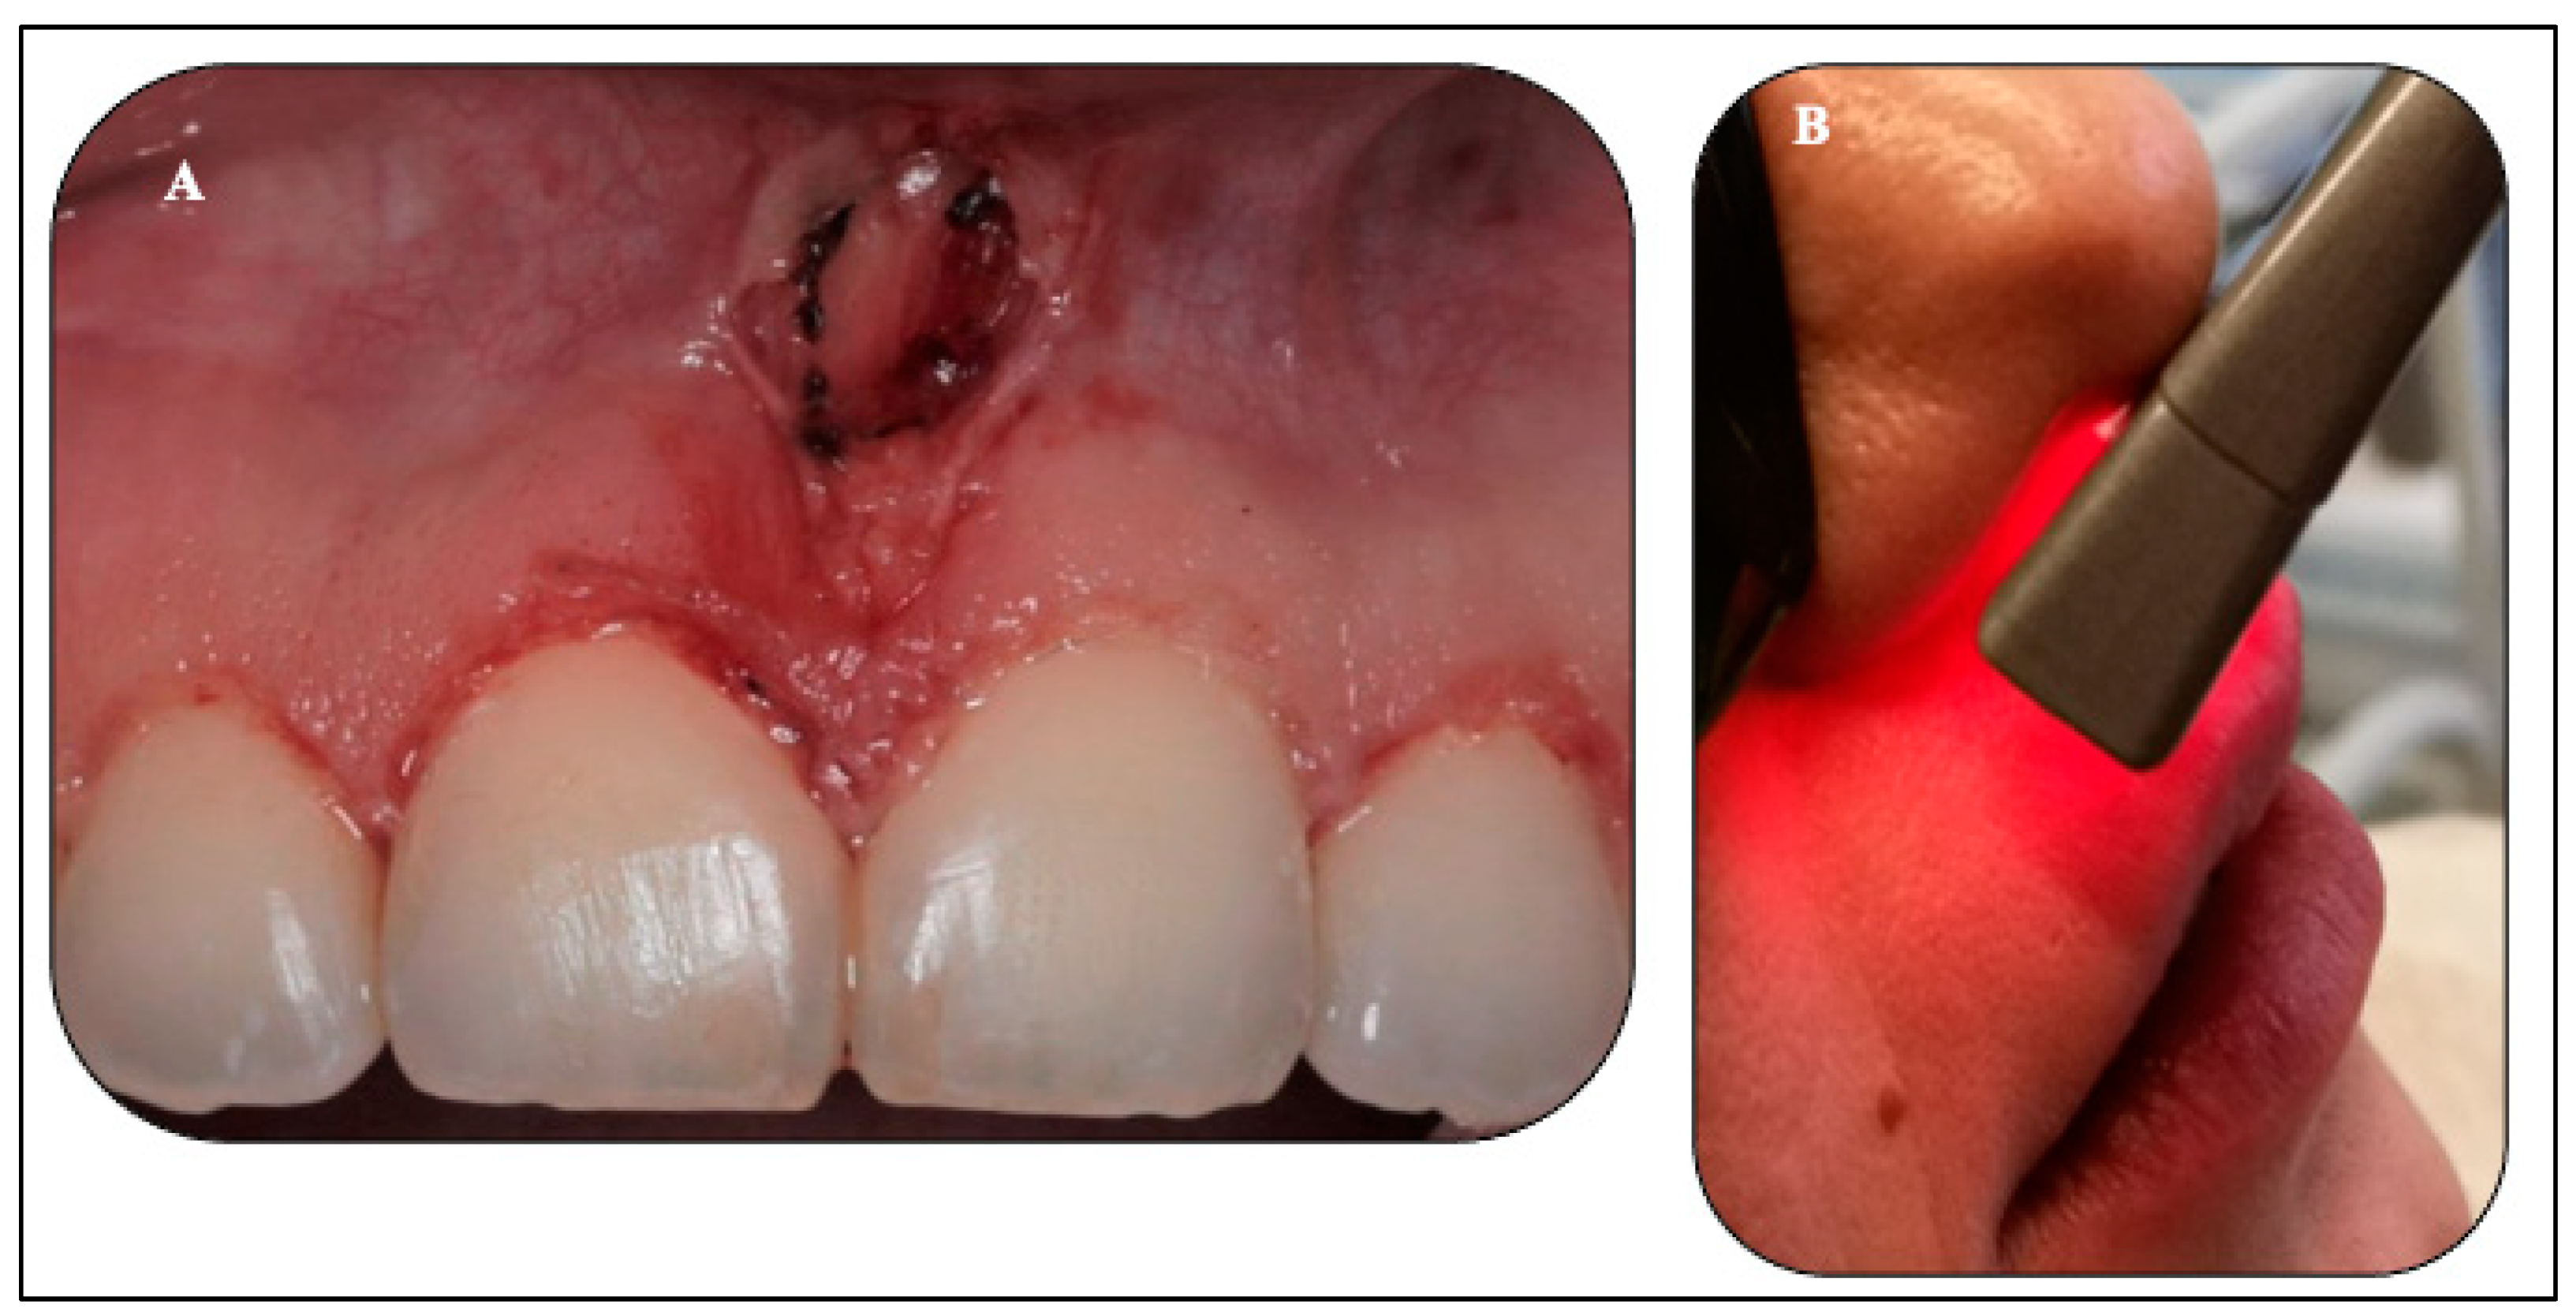

2.5.2. Upper Midline Frenectomy Procedure

2.5.3. Transcutaneous λ940 nm Laser-PBM (Extraoral Approach)